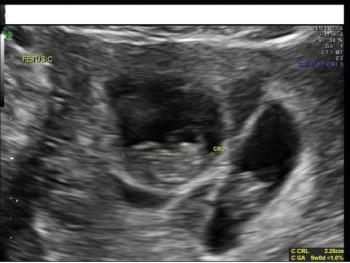

Ultrasound imaging is a key prenatal tool for revealing structural anomalies that may point to genetic conditions. This slideshow is Part 1 of our collection of ultrasound anomalies and includes first-trimester anomalies and second-trimester anomalies of the head and brain. Part 2 will discuss second-trimester anomalies of the body and limbs.